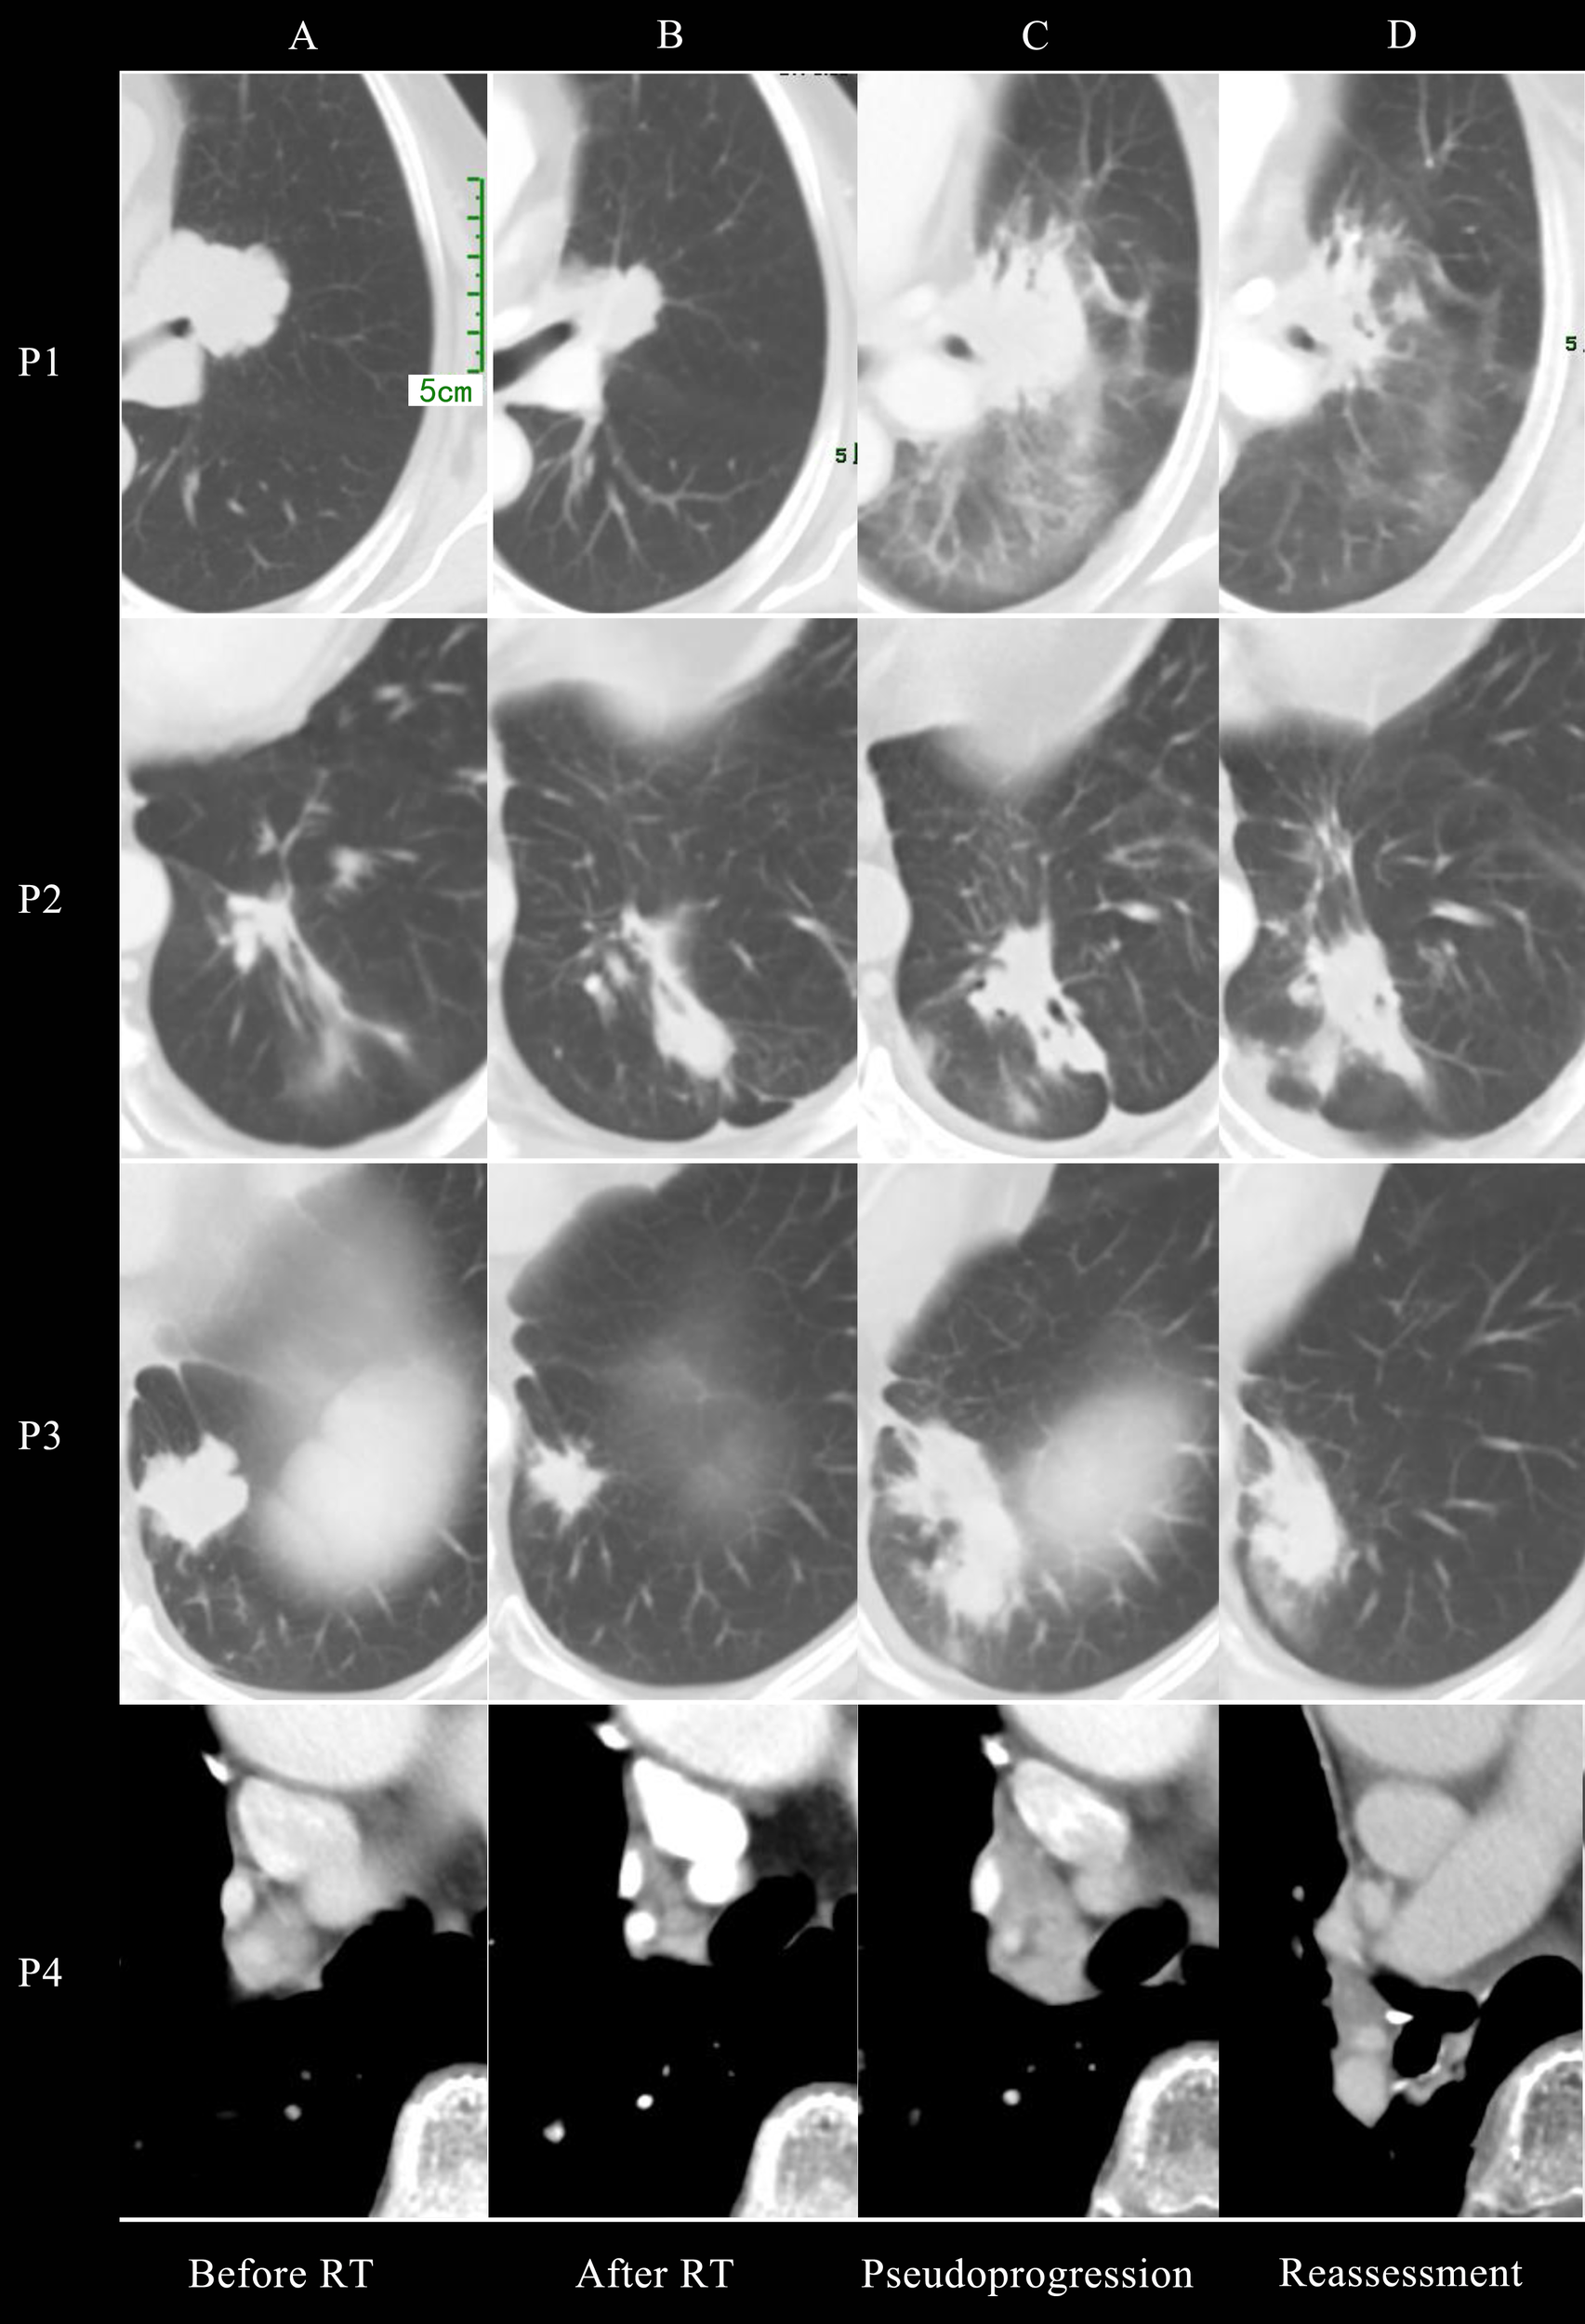

Figure 1 presented the thoracic radiological features of 4 patients. Before RT, Target lesions were all in PR or stable state. After thoracic RT, the first chest CT assessment showed that the target lesions in all 4 patients were reduced, among which 2 patients were evaluated as PR and 2 as SD. Pseudoprogression occurred at 0.8-3 months after RT or consolidation immunotherapy. According to RECIST 1.1 Criteria, all patients were evaluated as PD, but the target lesions did not significantly increase in further reassessment, therefore the target lesions are rated as iUPD based on iRECIST Criteria. None of the them had encountered an exacerbation of clinical symptoms, nor did they change their treatment regimen due to pseudoprogression.

Chest CT imaging of all 4 patients before radiotherapy (A), after radiotherapy (B), at pseudoprogression (C) and first reassessment after pseudoprogression (D).